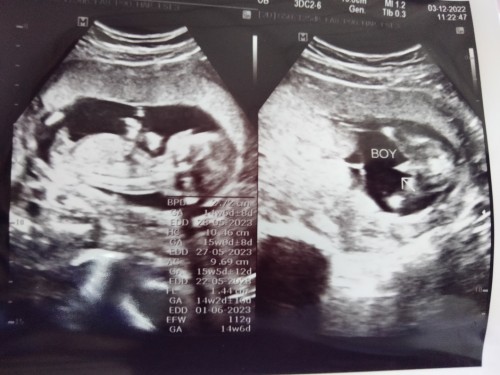

มีโอกาสหมออัลตร้าซาวด์เพศผิดมั้ยคะ ใจอยากได้ลูกสาว แต่หมอว่าเพศชาย ช่วยดูหน่อยค่ะ 😁

จุ๊ดจู๋ชัดมาก คงจะกลับลำยากแล้วล่ะค่ะแม่ 😂😂

โด่มาเลยค่ะแม่🤭น่าจะอดลุ้นแล้วมั้งคะ😆

ไม่น่าผิดค่ะ ชี้โด่มาเลย🤣

ลูกชายค่ะแม่☺️